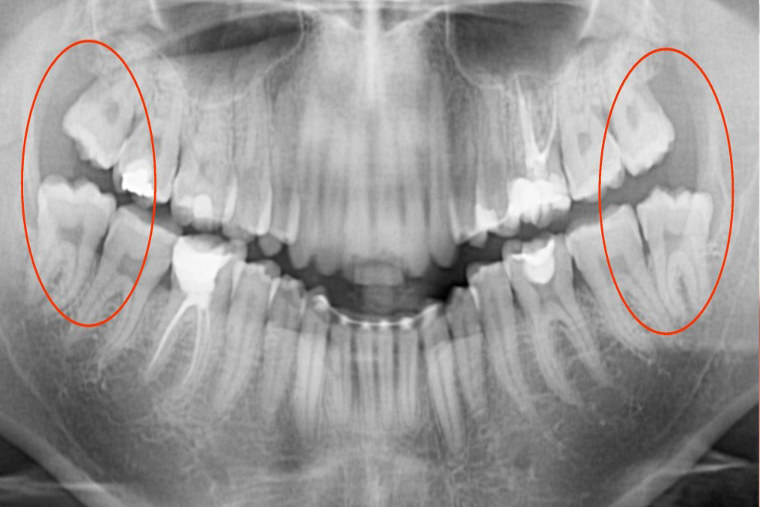

Zirugia

- “Juizioko Haginak eta betortzak” ateratzea